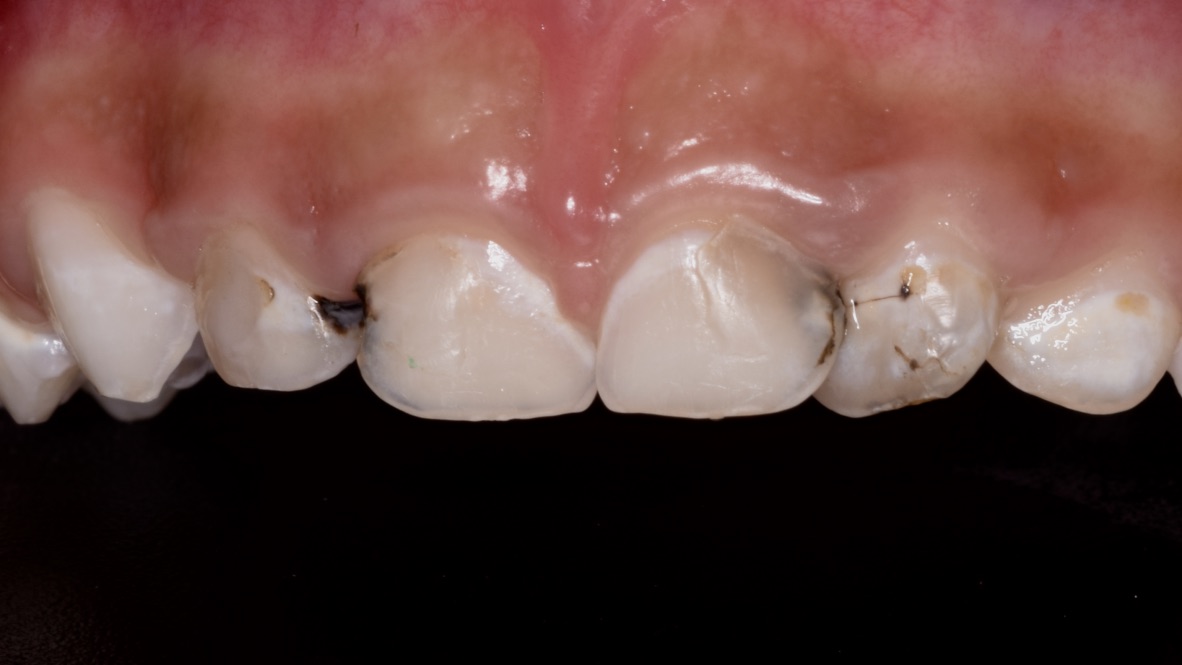

Presencia de lesiones de caries dental en los dientes de leche.

Las lesiones de caries dental son el reflejo de la enfermedad caries dental, y el primer signo clínico en los dientes son unas manchas blancas, opacas y rugosas que se desarrollan en las superficies de los dientes donde se acumula placa dentobacteriana con mayor facilidad, es decir, en las muelas, entre una muela y otra, o en la parte de adelante de los dientes cerca de la encía. Este tipo de lesión generalmente no produce dolor, pero requiere control por parte del odontopeditra. Cuando este tipo de lesiones avanzan, pueden afectar el esmalte y a la dentina y generar dolor provocado al consumir alimentos o bebidas, y en casos más severos, puede afectar el nervio del diente y haber dolor expontáneo.